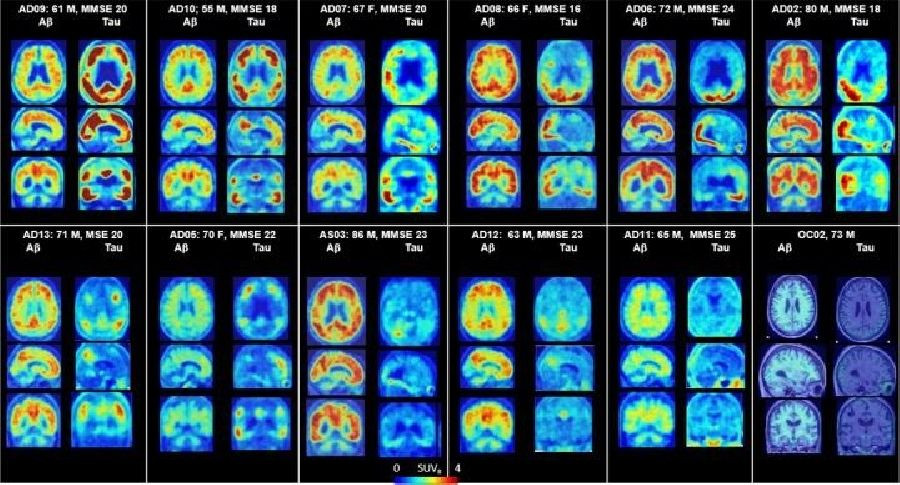

Para obtener una imagen más clara de los primeros efectos de la enfermedad de Alzheimer, los investigadores utilizaron imágenes de tomografía por emisión de positrones (PET) de una proteína que se encuentra en casi todas las sinapsis cerebrales.

Las tecnologías de imagen anteriores habían podido mostrar a grandes rasgos la pérdida de tejido cerebral o la reducción del metabolismo cerebral en el Alzheimer. Sin embargo, los nuevos escáneres PET muestran la distribución del daño sináptico, una patología más específica de la enfermedad presente en las primeras etapas de la enfermedad, dicen los autores.

El equipo de Yale recibió recientemente una subvención para realizar más imágenes sinápticas y relacionar la pérdida sináptica con otros marcadores de enfermedad para la enfermedad de Alzheimer, incluida la acumulación de amiloide y tau.